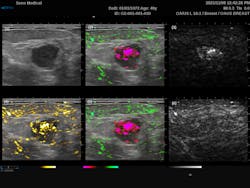

The most common endogenous chromophores used in PAI application are oxyhemoglobin (HbO2) and deoxyhemoglobin (HHb). These are particularly interesting for tumor screening due to the increased metabolic activity within cancer cells. The Imagio breast imaging system was explicitly designed for that exact purpose, combining dual-wavelength PAI with traditional ultrasound to produce a false-color overlay of blood content over a grayscale ultrasound image. This system utilizes dual 757 nm and 1064 nm excitation lasers to take advantage of the relatively high absorption of HHb compared to HbO2 at 757 nm, as opposed to 1064 nm where the relative absorption flips. From Figure 2, we can see the traditional grayscale ultrasound image of the mass in the first image, along with a map of the total blood in yellow (image 4) and the differentiated HHb in red and HbO2 in green (images 2 and 5). For the first time, this system provides clinicians with an FDA-approved real-time noninvasive means of identifying cancers without the need for ionizing radiation.PAI offers a significant improvement over MRI for vascular imaging since it does not require external contrast agents. Laser speckle contrast imaging (LSCI) can also detect subdermal blood flow,5 but it does not provide the spatial resolution needed to map the vascular architecture, nor can it monitor oxygenation. That said, it should be noted that the speed and non-contact nature of LSCI compared to PAI make it attractive for specific applications such as real-time interoperative blood flow monitoring.